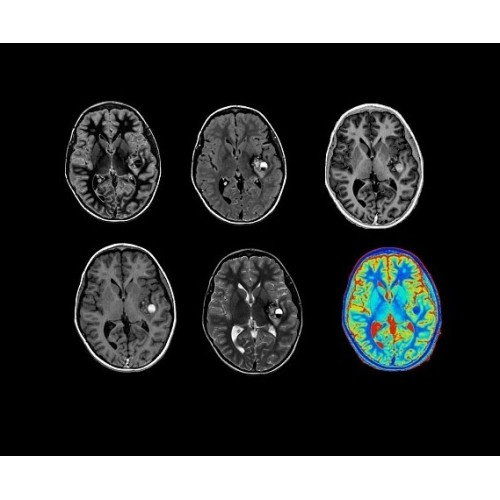

SIGNA PET/MR 3.0T — это гибридная система, в которой совмещаются две принципиально разные технологии — магнитно-резонансную томографию (МРТ) и позитронно-эмиссионную томографию (ПЭТ). Система отличающийся высокой чувствительностью и эффективностью и предназначена для диагностики в области онкологии, неврологии, кардио-васкулярных исследований, исследований воспалительных процессов.

Компания GE Healthcare представляет революционную, полностью интегрированную систему SIGNA PET/MR1, в которой сочетаются времяпролетная технология (TOF) и возможности напряженности магнитного поля 3.0 Тл. Мы поможем вам поднять исследования на более высокий уровень. SIGNA PET/MR позволяет достичь впечатляющей точности и скорости исследований, а благодаря новейшей технологии реконструкции Q.Clear2 качество изображений улучшается в два раза. Кроме того, в систему включен полный набор клинических приложений и гибких катушек для проведения любых видов исследования, открывая для вас возможности визуализации, о которых вы даже не догадывались.

Система SIGNA PET/MR предлагает впечатляющие клинические возможности и открывает доступ к наиболее полным пакетам программных приложений.

• Q.Clear — в основу технологии легли накопленные знания о том, как минимизировать помехи при реконструкции и получить четкое изображение. При значительном улучшении качества изображения сохраняется точность расчетов. Сочетание технологии TOF и реконструкции Q.Clear — ваш надежный помощник для получения точных и достоверных данных.

• Специальный пакет приложений для измерения и сравнения объемных изображений ЦНС с нормами поможет вам в диагностике нейродегенеративных заболеваний, а дополнительные инструменты визуализации — в постановке точного диагноза с помощью бета-амилоидов и радиоизотопных маркеров ФДГ.